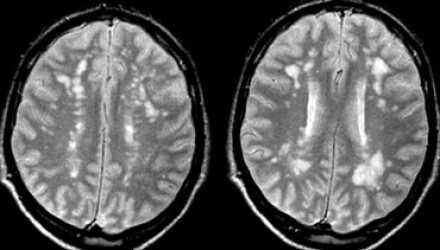

На серии МР-томограмм: множественные гиперинтенсивные участки в белом веществе головного мозга у пациента, страдающего гипертонической болезнью.

На МР-томограммах, представленных выше, визуализируются нарушения МР-сигнала в глубоких отделах больших полушарий. Важно отметить, что они не являются юкставентрикулярными, юкстакортикальными и не локализуются в области мозолистого тела. В отличие от рассеянного склероза, они не затрагивают желудочки мозга или кору. Учитывая, что вероятность развития гипоксически-ишемических поражений априори выше, можно сделать заключение о том, что представленные очаги, вероятнее, имеют сосудистое происхождение.

Только при наличии клинической симптоматики, непосредственно указывающей на воспалительное, инфекционное или иное заболевание, а также токсическую энцефалопатию, становится возможным рассматривать очаговые изменения белого вещества в связи с этими состояниями. Подозрение на рассеянный склероз у пациента с подобными нарушениями на МРТ, но без клинических признаков, признается необоснованным.